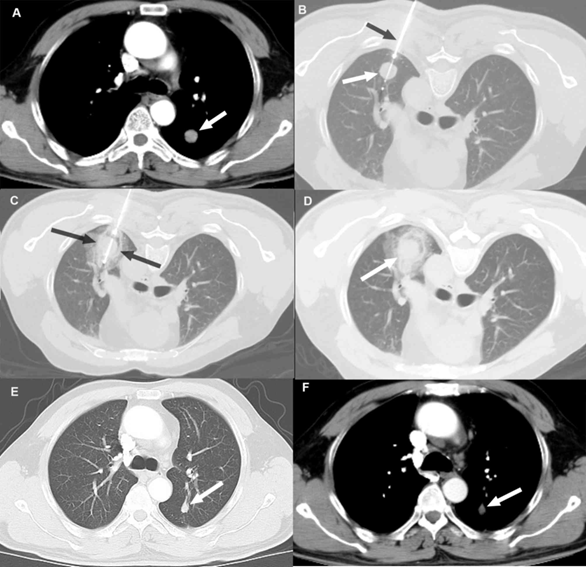

治療層面而言,透過低劑量電腦斷層找到的早期肺癌,多數能以手術治療或治癒,由於早期肺癌手術透過"電腦斷層導引之肺臟細針定位術" (圖1) 所切除的肺部組織相對較少,對於患者術後的肺功能與生活品質的影響很小。即使患者不適合手術或不願意接受手術,也可以選擇用"冷凍消融術治療" (圖2),對於初期肺癌也可以達到很好的腫瘤控制。

(圖一) 肺臟細針定位術是利用電腦斷層的定位與導引,透過細針經皮穿刺把定位線埋入病灶周邊,或者把染料注入病灶周邊,以利手術中辦識病灶,進行外科切除及病理檢查。 |

(圖二)